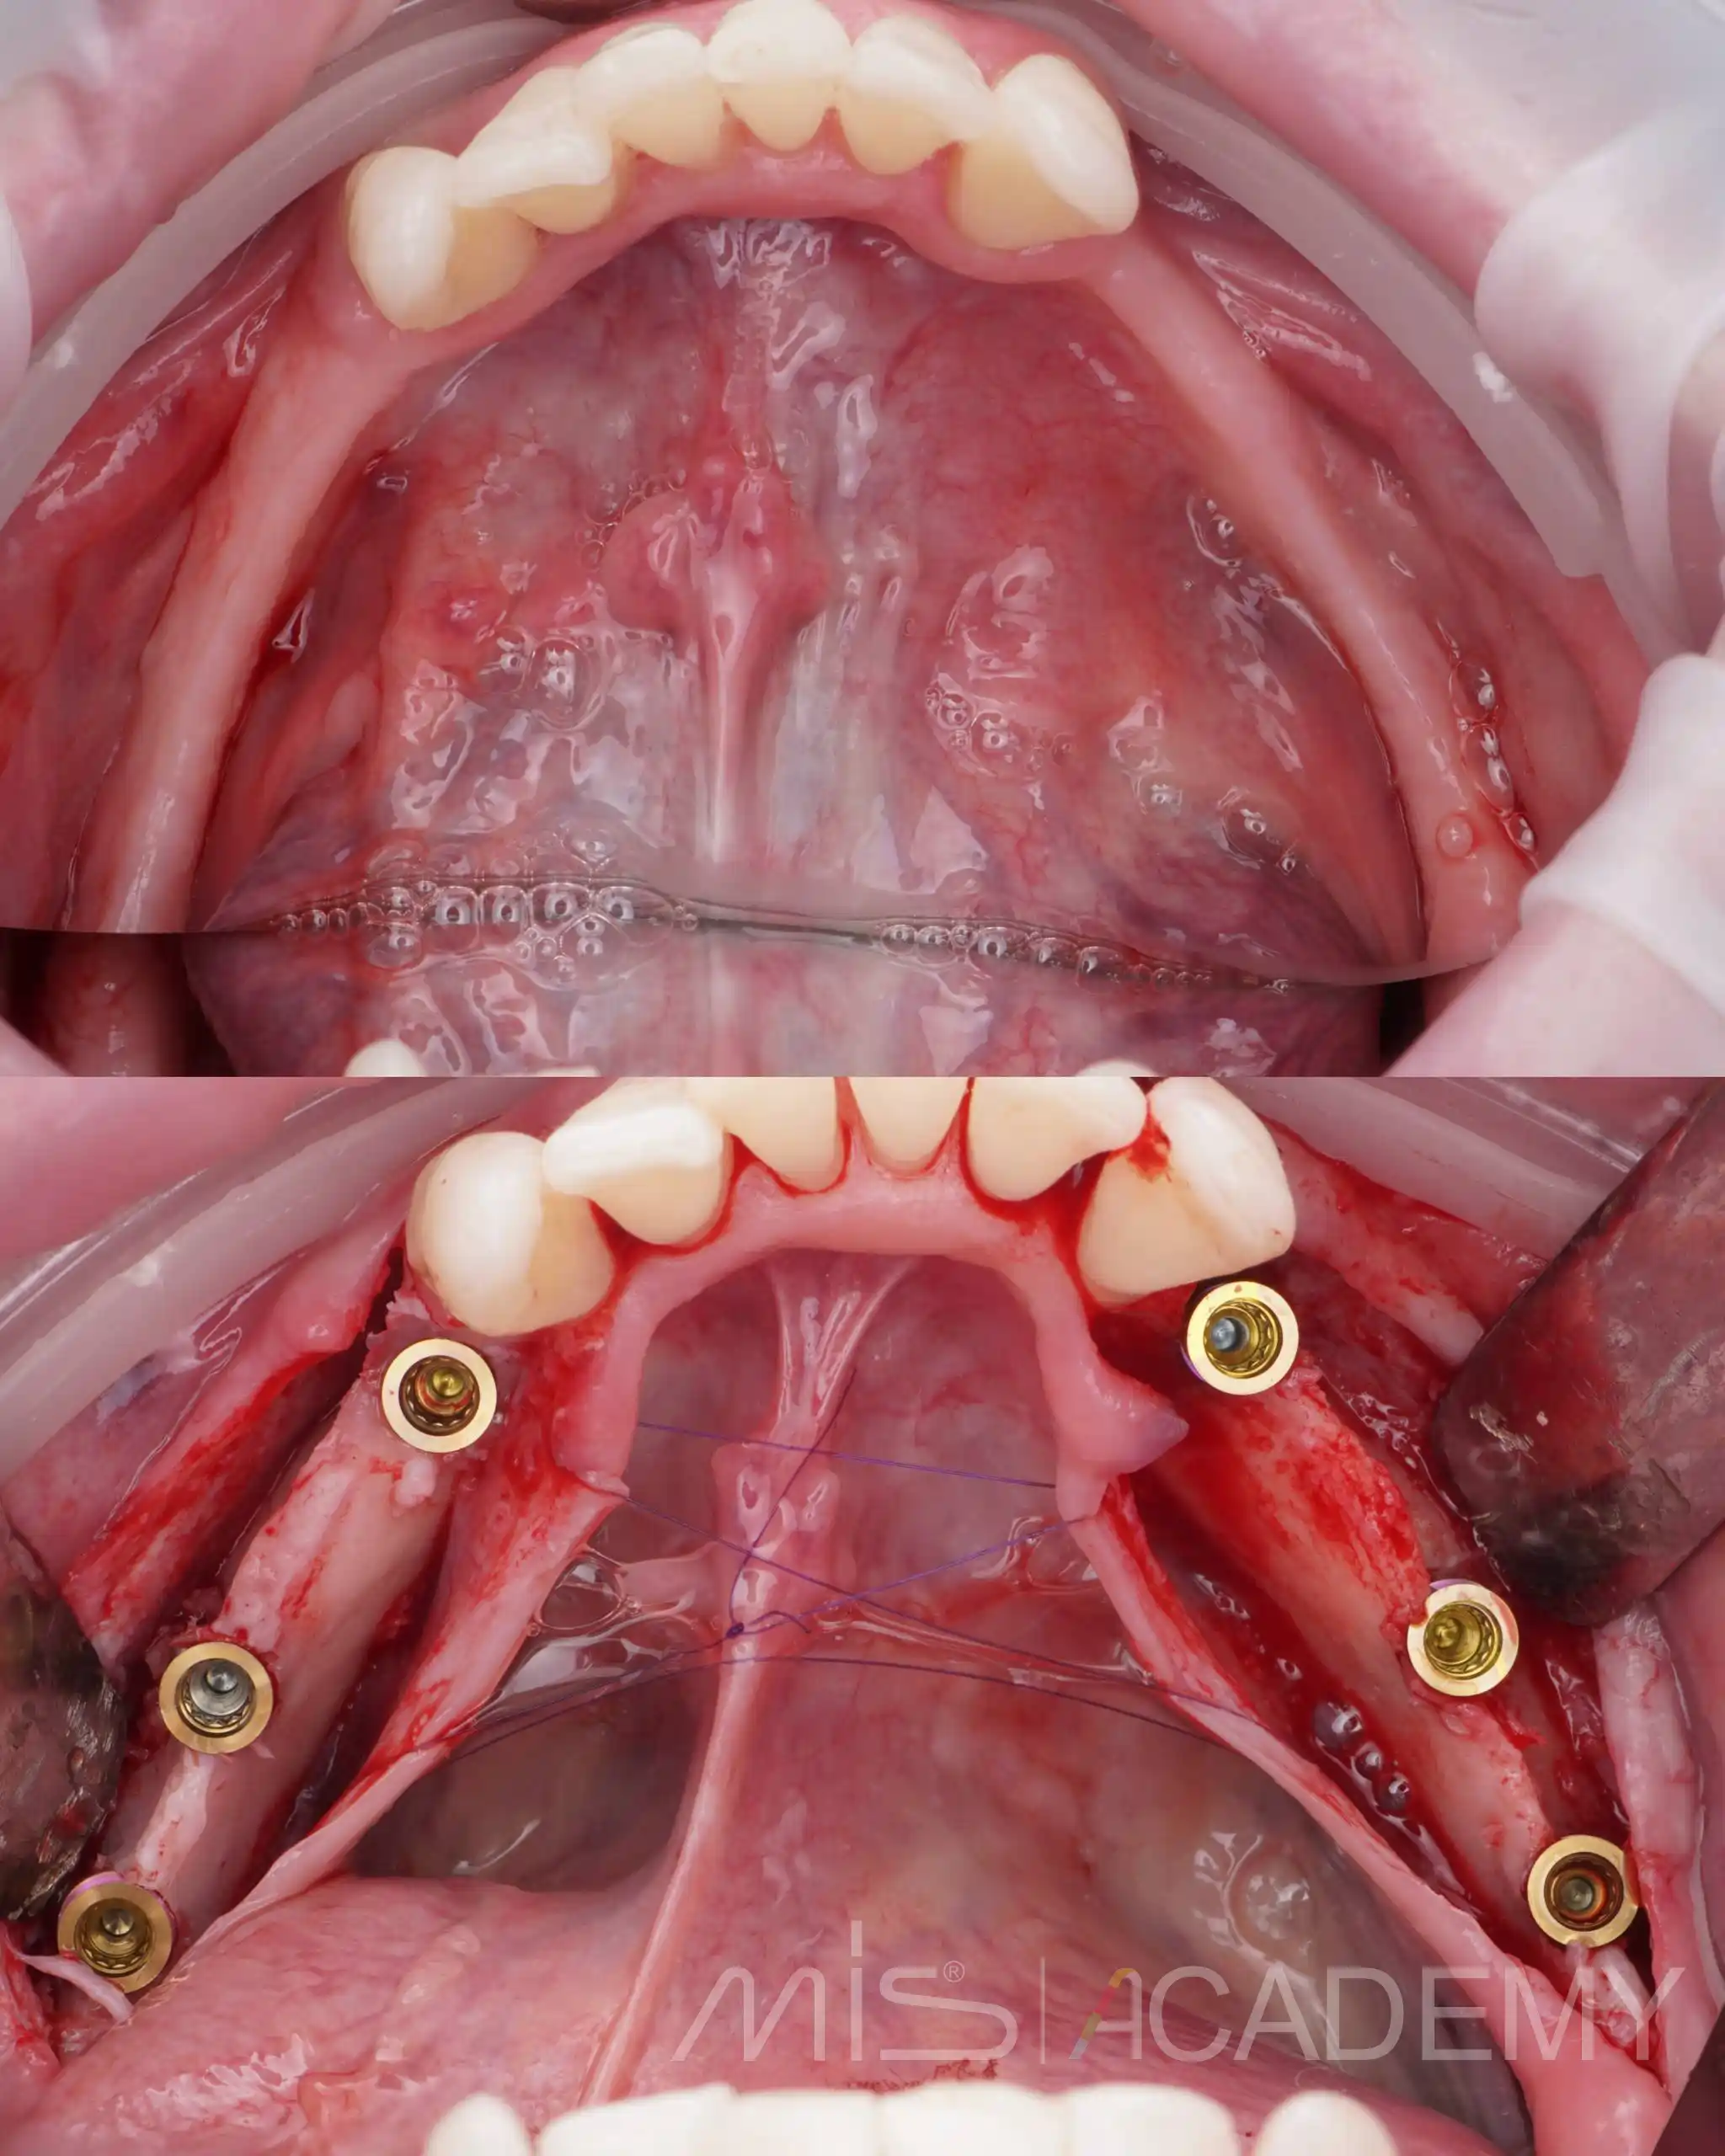

— По навигационному накостному шаблону установили 6 имплантатов MIS C1.

— В дистальных отделах выполнены открытый и закрытый синуслифтинги под заглушки.

— Четыре имплантата в переднем отделе нагружены временной армированной конструкцией, разборная балка сварена непосредственно в полости рта, с уровня коннектов и угловых мультиюнитов.

Второй этап нижняя челюсть:

В боковых отделах выраженная атрофия по ширине и высоте. При планировании приняли решение об имплантации с одновременной костной аугментацией по ширине.

— Установлены имплантаты MIS C1.

— Connect абатменты с заглушками, которые дополнительно сработали как тенты.